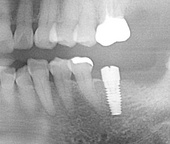

まず午前は右下2本の植立です。いつもお世話になっている麻酔医の元橋先生にも駆け付けて頂き、静脈内鎮静法にて対応いたしました。

午後は左下1本の植立です。こちらも術式自体特に問題もなくスムーズに進みました。